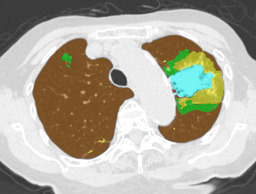

In this paper, we define partial annotation as an annotation format in which only one class is chosen for the annotation and only pixels belonging to the chosen class are annotated per image. For example, in Figure 1(a), although there is ground glass opacity in the image, only consolidation is chosen for annotation and pixels of consolidation are annotated. Partially annotated dataset is less informative for training, however, it is much easier to create compared to fully annotated dataset since annotators only need to focus on one class at a time during the annotation task.

Statistics of our dataset are shown in Table 1 and typical images and their annotations for each DLD pattern are shown in Figure 1. In our partially annotated dataset, all the pixels in a slice were manually classified into two classes: dominating DLD pattern and other tissues. In other words, all the pixels in our dataset were assigned one of the labels from either of the two label sets, Lstrong={lCON,lGGO,lHCM,lEMP,lNOR}subscript𝐿𝑠𝑡𝑟𝑜𝑛𝑔subscript𝑙𝐶𝑂𝑁subscript𝑙𝐺𝐺𝑂subscript𝑙𝐻𝐶𝑀subscript𝑙𝐸𝑀𝑃subscript𝑙𝑁𝑂𝑅L_{strong}=\{l_{CON},l_{GGO},l_{HCM},l_{EMP},l_{NOR}\} or Lweak={lCON¯,lGGO¯,lHCM¯,lEMP¯,lNOR¯}subscript𝐿𝑤𝑒𝑎𝑘subscript𝑙¯𝐶𝑂𝑁subscript𝑙¯𝐺𝐺𝑂subscript𝑙¯𝐻𝐶𝑀subscript𝑙¯𝐸𝑀𝑃subscript𝑙¯𝑁𝑂𝑅L_{weak}=\{l_{\overline{CON}},l_{\overline{GGO}},l_{\overline{HCM}},l_{\overline{EMP}},l_{\overline{NOR}}\}. For example, in Figure 1(a), colored pixels were labeled as lCONsubscript𝑙𝐶𝑂𝑁l_{CON} and all the other pixels were labeled as lCON¯subscript𝑙¯𝐶𝑂𝑁l_{\overline{CON}}. In this paper, we call pixels of label lLweak𝑙subscript𝐿𝑤𝑒𝑎𝑘l\in L_{weak} and lLstrong𝑙subscript𝐿𝑠𝑡𝑟𝑜𝑛𝑔l\in L_{strong} as weakly annotated pixels and strongly annotated pixels respectively. Our pixel-wise annotations were created in the following steps. First, up to 3 slices were chosen for the annotation for each HRCT scan and for each slice, one representing DLD pattern was chosen by a radiologist. Second, three radiologists performed pixel-wise binary annotation (e.g. binary annotation between lCONsubscript𝑙𝐶𝑂𝑁l_{CON} or lCON¯subscript𝑙¯𝐶𝑂𝑁l_{\overline{CON}}) for each slice. Finally, the radiologists’ annotations were merged by taking majority classes for each pixel (i.e. pixels labeled as a DLD pattern by more than 2 radiologists became the corresponding DLD pixel). In addition to the DLDs annotation, lung fields were manually segmented under the supervision of radiologists and training and testing were conducted only within the lung fields.

Figure 1: Typical slices for each DLD classes. Slices of HRCT are shown in lung window setting (window-center=-600, window-width=1500) with annotated labels superimposed in transparent colors. Note that even if more than one DLD patterns existed, only one DLD pattern was chosen and annotated for a slice to facilitate the annotation process.